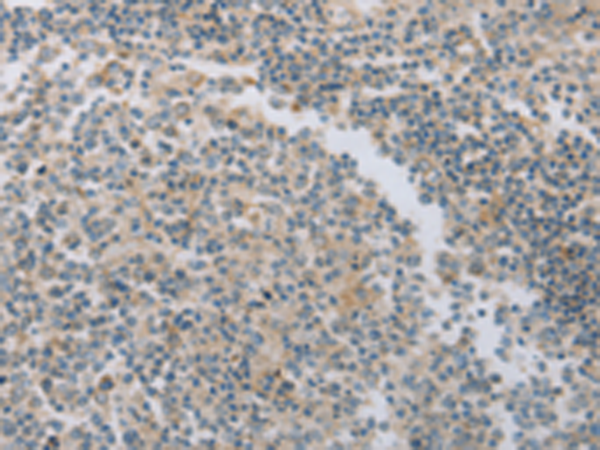

分类: 科研抗体货号: P07452别名: ME; HME; MME; MMP-12应用: WB,IHC反应种属: Human